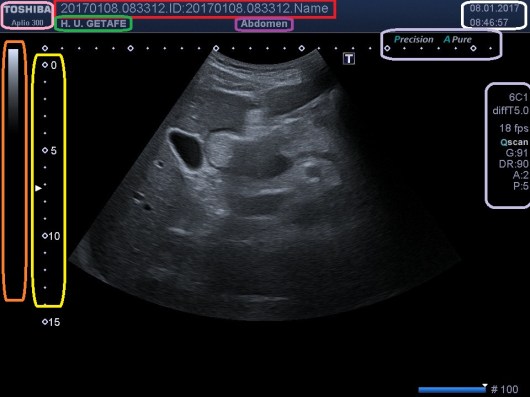

El resultado será lo más parecido a esto:

En la imagen podemos ver, posterior a la Vejiga (anecoica), una estructura ovalada, hipoecogénica y homogénea, que es la Próstata, a la que le realizamos tres medidas para obtener un volumen:

• Derecha-Izquierda (Corte Transverso)

• Antero-Posterior (Corte Transverso)

• Cráneo-Caudal (Corte Longitudinal)

Estos tres cortes son indispensables para conseguir el volumen de la estructura, que previamente, en nuestro menú, habremos activado entrando en MEDIDAS y seleccionando la opción de VOLUMEN, que en cada casa comercial, será de una manera determinada.

Medidas y Volumen en cm3.